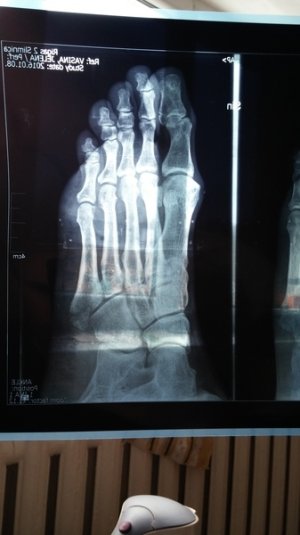

Здравствуйте. Мне 38 лет. Перелом 5-ой плюсневой.

Приложенные снимки - на следующий день после случившегося. Сразу в гипс на 5 недель. Ни в травмпункте, ни в поликлинике лечащий врач даже на упоминали операцию.

Только в травмпункте доктор сказал "... с незначительным смещением, поэтому просто гипс на месяц."

Посмотреть вложение 13116 Посмотреть вложение 13117